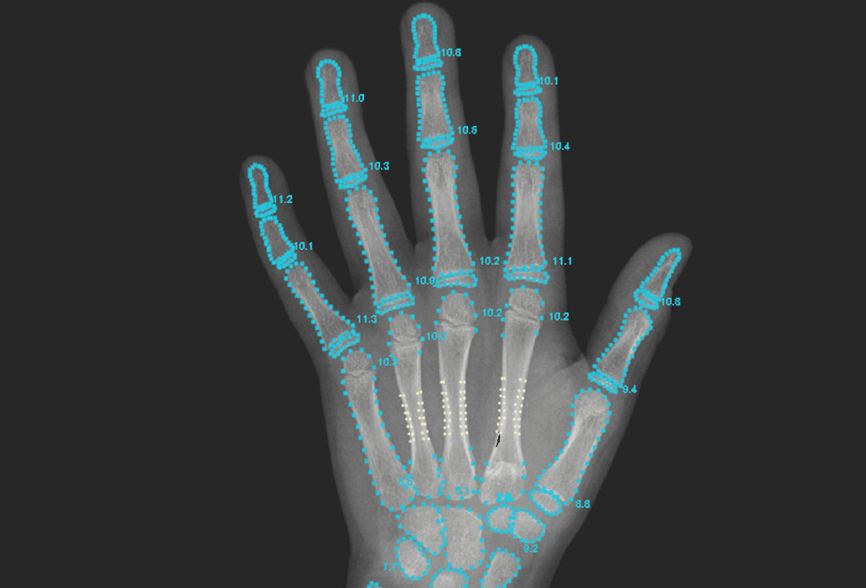

骨年齢判定は成長予測に重要ですが、従来は医師の目視でばらつきが生じることもありました。当院ではAI解析システムを導入し、数分で信頼性の高い判定を実現。医師の判断と組み合わせ、より正確な成長評価を行います。

成長ホルモン療法を検討するにあたり、当院ではまず、お子さま一人ひとりの成長状態を医学的、多角的に評価します。具体的には、骨の成熟度を示す「骨年齢」や、これまでの成長の推移を示す「成長曲線」、血中ホルモン値やご両親の身長などの遺伝的背景といった複数の指標をもとに、総合的かつ慎重に評価を行います。